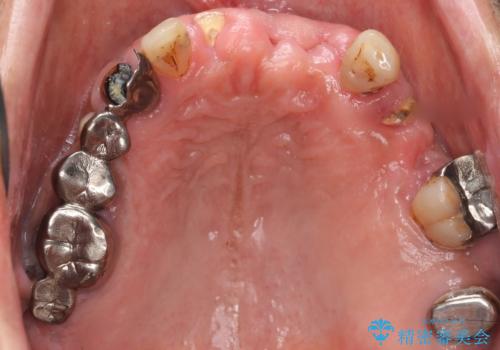

- 交通事故により前歯が折れたことを主訴に来院された患者様です。

精査したところ、前歯以外にも歯が折れており、上の歯の多くが保存不可能な状態でした。

インプラントと入れ歯の治療方針を提案したところ、なるべく予算を抑えたいとのことで入れ歯による治療をご希望されました。

保存可能な2本の歯を用いて、マグネットデンチャー(磁性アタッチメントを用いた入れ歯)による治療を行いました。